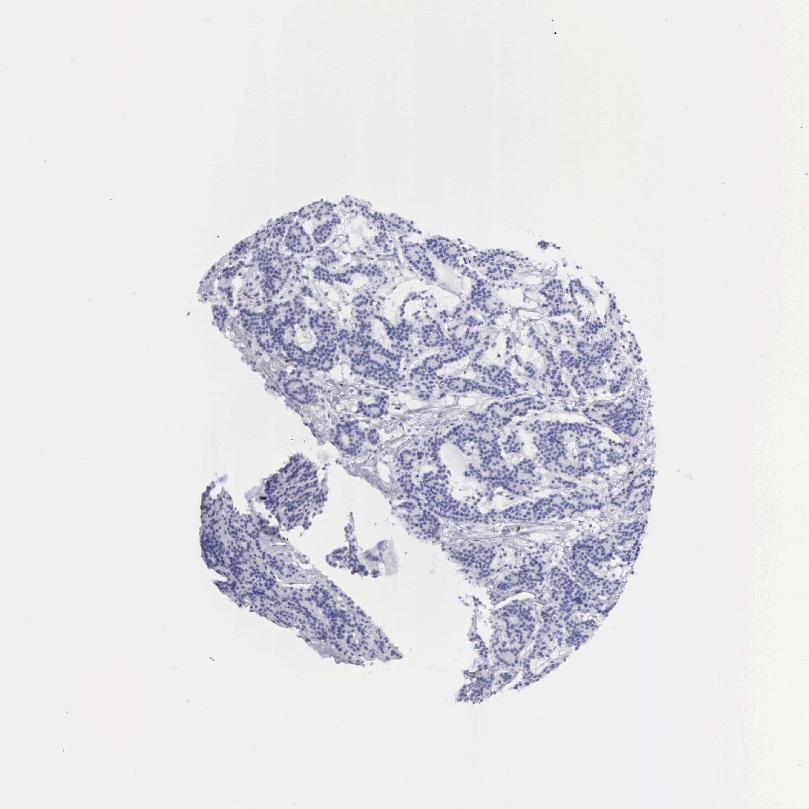

TISSUE PRIMARY DATA PARATHYROID GLAND Show tissue menu

PARATHYROID GLAND - Antibody stainingi

Antibody staining in the annotated cell types in the current human tissue is reported as not detected, low, medium, or high, based on conventional immunohistochemistry profiling in selected tissues. This score is based on the combination of the staining intensity and fraction of stained cells.

Each image is clickable and will lead to virtual microscopy that enables deeper exploration of all samples and also displays staining intensity scores, fraction scores and subcellular localization as well as patient and tissue information for each sample.

Antibody HPA000937Antibody CAB002520

Glandular cells Not detectedNot detected